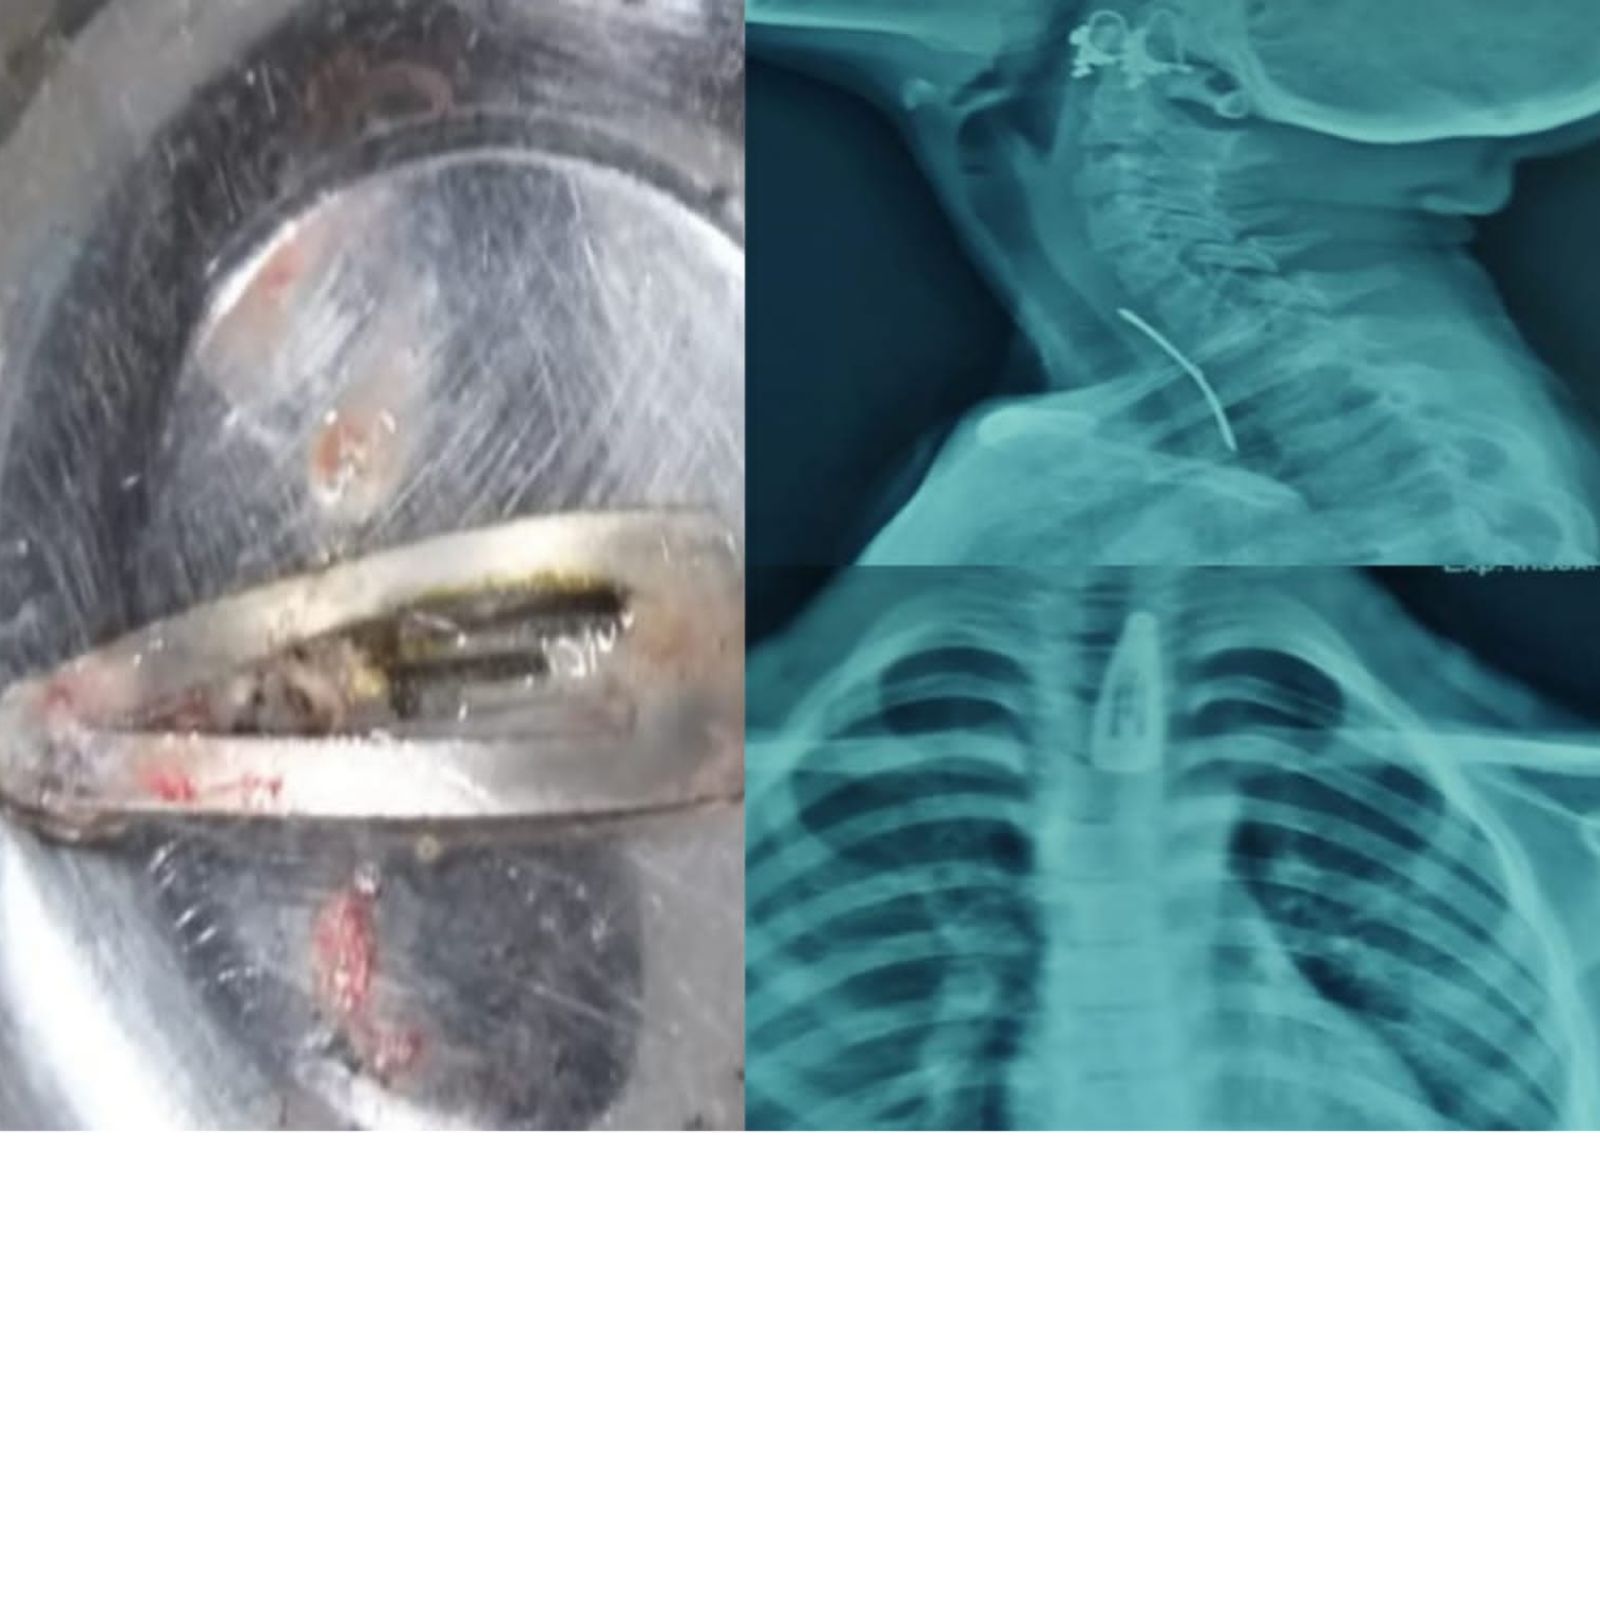

एक्स रे पाहून बाळाचे आई-वडील पुरते घाबरले.

अमित राय/कोल्हापूर : कोल्हापूरातील एका सात वर्षांच्या बाळाने महिलांच्या केसातील पिन गिळल्याचा प्रकार समोर आला आहे. शस्त्रक्रियाद्वारे डॉक्टरांनी यशस्वीपणे ही पिन बाहेर काढली. बाळाला गिळताना आणि छातीत त्रास होऊ लागल्याने त्यांनी तात्काळ येथील सीपीआर रुग्णालयात दाखल केले होते. त्यानंतर एक्स-रे मध्ये बाळाने केसांतील पिन गिळल्याचे दिसून आले. त्यानंतर तत्काळ वेळ न घालवता डॉक्टरांनी दुर्बिणीद्वारे अन्न नलिकेतून ही पिन बाहेर काढली. जवळपास दीड सेंटीमीटर लांब ही पिन होती. सद्या बाळाची प्रकृती ठीक असल्याचे डॉक्टरांनी सांगितले आहे. अनेकदा लहान मुलांकडे थोडंही दुर्लक्ष केलं तरी महागात पडू शकतं. त्यामुळे पालकांनी अधिक सजग राहणं आवश्यक आहे. सेल, पिन किंवा आकाराने लहान वस्तू लहान मुलांच्या आजूबाजूला ठेवणं टाळावं. काही मुलं नाणी देखील गिळल्याच्या अनेक घटना समोर आल्या आहेत. सेलही गिळल्याच्या घटना समोर आल्या असून हे धोकादायक आहे. त्यातून अनर्थ घडू शकतो. कोल्हापूरमध्ये मुले पळवल्याच्या अफवेनं खळबळ, पोलिसांनी थेट काढला आदेश कोल्हापुरातील या घटनेत वेळेत बाळाला डॉक्टरांकडे नेल्याने त्याचा जीव बचावला आहे. त्याला गिळण्यास त्रास होत असल्याने याचा उलगडा झाला. एक्सरेमध्ये पिनचा आकारही दिसून येत आहे.